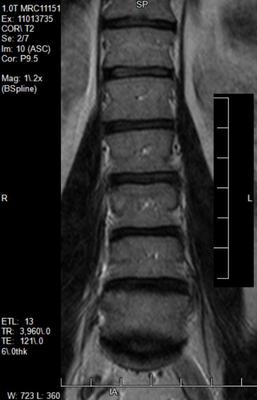

Most pain is on left side lower back with tension down back right leg. Pinching feeling also behind left side back knee at times. Please see 4 mri images.

The scans show possibly small bulges at the lower two levels. More important for me are the clinical findings; bulging discs in normal people are common.